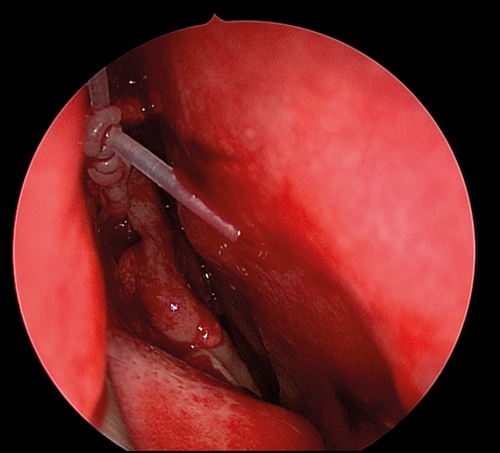

Figure 6. O’Donaghue tube in place with mucosal flaps laid back.

The medial wall of the sac is tented medially using the end of the O’Donaghue probe and incised vertically using a sharp pointed Phaco knife at its most anterior aspect (see Figure 3). The aim is to create a large posterior based sac flap, which can later be folded back towards the uncinate process, facilitating full sac marsupialisation. Relieving incisions are then placed horizontally, both superiorly (see Figure 4) and inferiorly (see Figure 5) to complete the sac incision into a ‘C’ shape. The remaining posterior edge is left intact but the completed sac wall flap can now be folded posteriorly, exposing the entire sac lumen. The lacrimal probe should be visible and is pulled through with Mosquito artery forceps. The process is repeated with the probe and stent through the superior canaliculus. Upon delivery of the stents a Watzke sleeve is placed and the stents are tied. The lacrimal sac flaps remain folded backwards but the nasal mucosal flaps are repositioned to overlap each sac flap to encourage healing and ensure there is no exposed bone (see Figure 6).